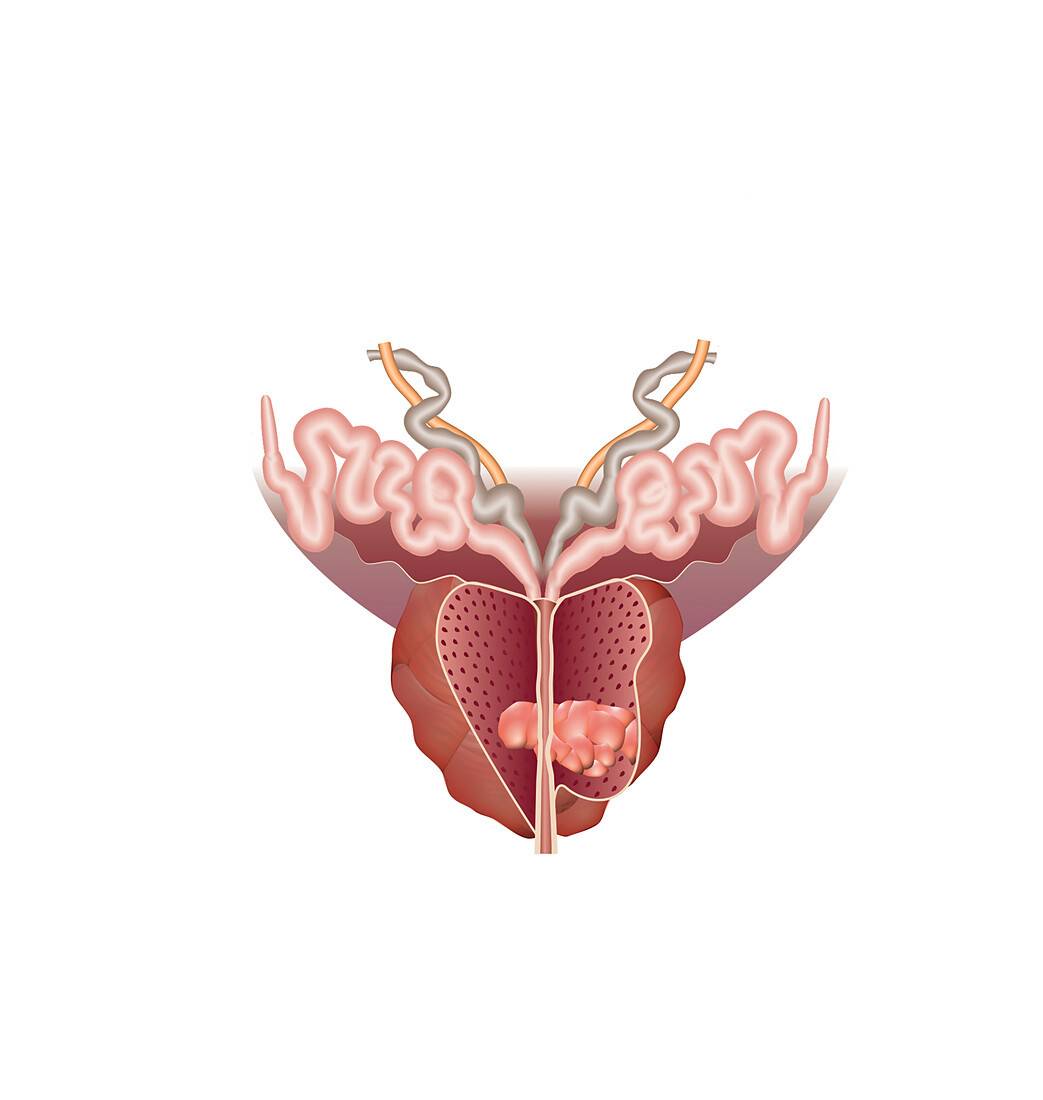

Le cancer de la prostate

La prostate est une glande de l’appareil génital masculin, qui joue un rôle dans la production du sperme.

En 2019, Jiang et al. ont décrit un modèle simple de prostate sur puce qui reproduisait l'interface stroma-épithélial [49]. Ce dispositif (Figure 4) est constitué de deux canaux superposés en PDMS (pour polydiméthylsiloxane) séparés par une membrane microporeuse en polyester, ce qui a permis une communication paracrine1 entre les cellules cancéreuses et les cellules du stroma tout en empêchant un contact direct entre les deux types de cellules afin d'étudier les voies de signalisation biochimique dans l'interface stroma-épithélial2. La communication biochimique entre les cellules épithéliales, stromales et cancéreuses est un facteur clé de la physiopathologie du cancer de la prostate.

Modèle de cancer du sein de stade précoce : la surface supérieure contient des cellules épithéliales et la surface inférieure un hydrogel de matrice extracellulaire contenant des fibroblastes. [54]